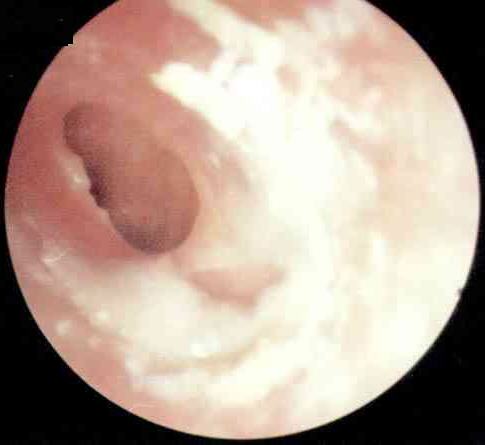

中耳炎病理图

西安新城中大耳鼻喉医院耳科张全安教授介绍,对于耳朵流脓,许多人都认为没什么了不起,是小毛病。但事实上,由于人的耳部与头颅内的脑膜很接近,中耳若感染发炎,可以通过血液循环或是通过内耳直接扩展到颅内,而引起颅内的并发症,严重时可以危及患者的生命安全。经过检查发现,刘先生属于化脓性中耳炎,病灶已侵犯到脑部造成脑脓肿从而导致头部剧烈疼痛,这个时候如果脓肿破裂则随时有生命危险。随后冯亮医生为他实施““全安”系统疗法”,有效解除了隐患。

慢性中耳炎按患病时间、病情轻重不同分为三种:单纯性,脓疡性和胆脂瘤性。它们共同的表现是均有耳流脓,反复不止,有时脓液中还混有血性分泌物;另外,有耳鸣及听力下降,如果出现并发症,会有眩晕和头痛。